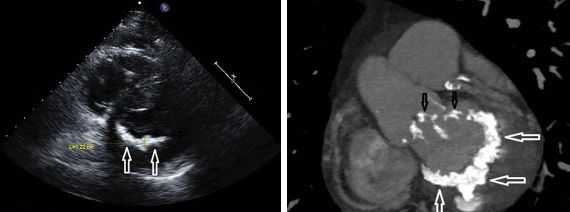

- ЭхоКГ. При УЗИ сердца обнаруживается гипертрофия стенок и расширение полости правого желудочка, наличие трикуспидальной регургитации, снижение показателя систолической экскурсии трикуспидального кольца (TASPE). Для уточнения данных выполняется трехмерная эхокардиография в режиме реального времени (RT3DE).

- Рентгенодиагностика. При рентгенографии органов грудной клетки определяется увеличение размеров и деформация контуров сердца, повышение прозрачности периферических отделов легких, выпячивание ствола легочной артерии. Для более точной визуализации внутрисердечных структур применяется КТ.